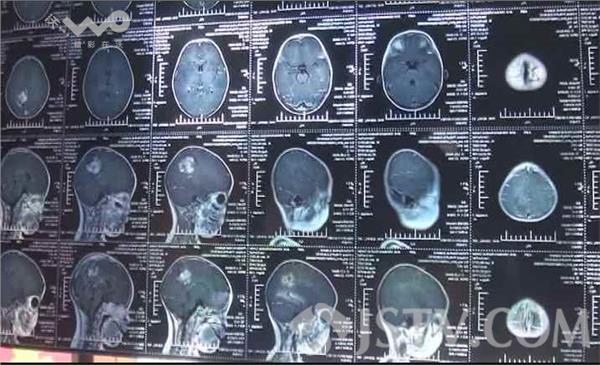

记者赶到射阳县经济开发区合东村海东一巷八号颜章胜的家中时,他正抱着小孩站在家中的院子里,小孩在不停地哭闹。颜章胜告诉记者,去年6月份的一天,突然发现小孩的大便排不出来,到医院检查后确诊为卵黄囊瘤,后来就在上海做了化疗和手术切除,前后一共做了四次手术和十次的化疗,共花费了四十多万元的医疗费用,其中有近四十万元是从亲戚朋友处借的,还有一部分是爱心人士捐助的。由于孩子的肿瘤长在肛门附近,在进行手术、化疗过程中,为防止刀口被感染,医生在孩子的腹部切开一个切口,用来排泄粪便。然而,让颜章胜没有想到的是,今年6月份检查时,发现孩子的各项指标又出现异常,在进一步的详细检查后,医生得出了小孩脑子里有一个转移瘤,必须要开刀切除、再进行化疗等一系列的治疗,才有希望能保住孩子的生命。